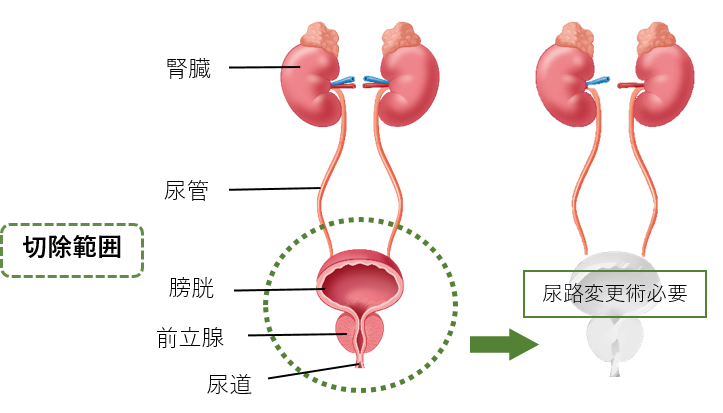

究める鏡視下膀胱全摘術・尿路変向術 Level up LRC, RARC | 三木。メジカルビュー社|泌尿器科|究める鏡視下膀胱全摘術・尿路変向。ロボット支援膀胱全摘除術(RARC) | 岩手医科大学 泌尿器科学講座。★3月精米★ 令和6年産 福井県産 いちほまれ 5kg 白米 精米。膀胱がん【泌尿器科疾患について】 - 東京慈恵会医科大学 泌尿器科。膀胱がん|KOMPAS。手術手技(膀胱全摘除術) | 領域情報 | アステラスメディカルネット。膀胱がん|KOMPAS。周術期の負担を軽減し早期社会復帰を!「ロボット支援腹腔鏡下。腎盂尿管移行部狭窄症に対するロボット支援腹腔鏡下腎盂形成術。朝倉書店『内科学』(第12版)デジタル付録。腹腔鏡下尿膜管摘出術及び左腎摘出術 - Olympus Professional。ロボット手術の定番!新品、未使用です。間違って2冊買ってしまったので、ページを開いてもいないため、本屋さんの「売上スリップ」も付いたままの全くの新品です。膀胱がんの外科治療について | 小野薬品 がん情報 一般向け。